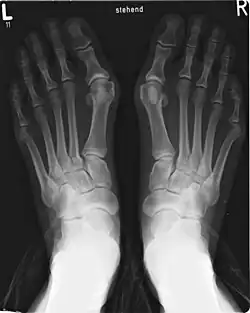

Hallux valgus mit deutlich sichtbarer Abknickung des ersten Mittelfußknochens nach innen

Bei einer Hallux-valgus-Fehlstellung kommt es im ersten Tarsometatarsalgelenk zu einer medialen Abduktion zum Fußinnenrand und einer Varus-Fehlstellung des ersten Mittelfußknochens (Metatarsus primus varus). Entsprechend setzen einige Operationsverfahren zur Korrektur des Hallux valgus an diesem ersten Tarsometatarsalgelenk an, besonders die Lapidus-Arthrodese als korrigierende Versteifung des Gelenks.